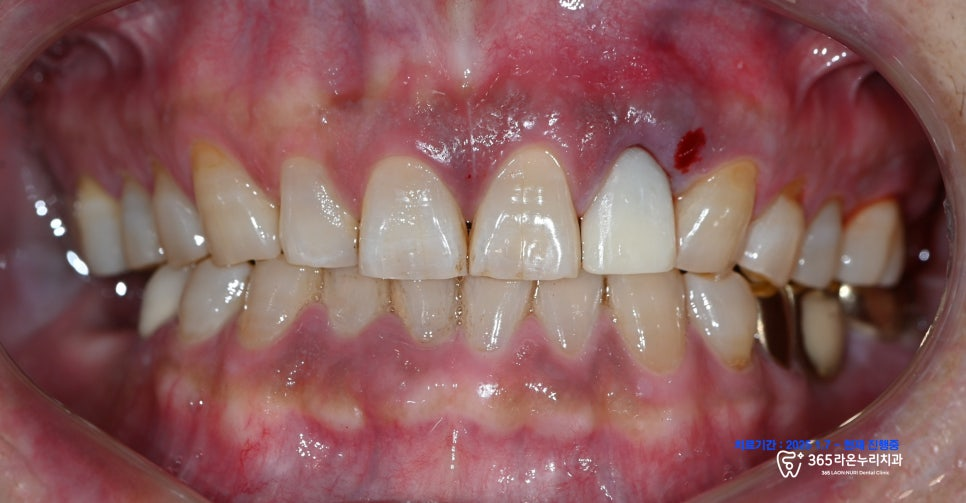

그렇게 서지컬 가이드를 이용해

좋은 방향으로 심어졌습니다.

그리고 앞니 치료를 진행하는 동안

사용하실 임시 치아도 예쁜 형태로

완성되었습니다.